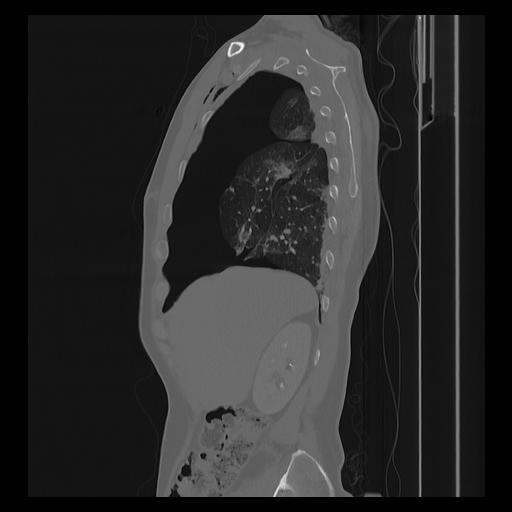

33 PULMON,CE,Sagittal,3.000,PULMON,Sagittal,